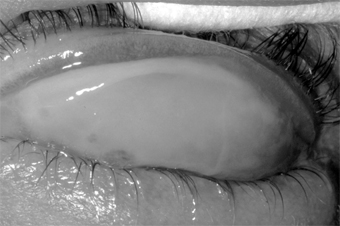

Epidemic keratoconjunctivitis is usually bilateral. The onset is often in one eye only, however, and as a rule the first eye is more severely affected. At onset the patient notes injection, moderate pain, and tearing, followed in 5-14 days by photophobia, epithelial keratitis, and round subepithelial opacities. Corneal sensation is normal. A tender preauricular node is characteristic. Edema of the eyelids, chemosis, and conjunctival hyperemia mark the acute phase, with follicles and subconjunctival hemorrhages often appearing within 48 hours. Pseudomembranes (and occasionally true membranes) may occur and may be followed by flat scars or symblepharon formation (Figure 5-5).

Figure 5-5

Figure 5-5: Epidemic keratoconjunctivitis. Thick white membrane of upper palpebral conjunctiva.

The conjunctivitis lasts for 3-4 weeks at most. The subepithelial opacities are concentrated in the central cornea, usually sparing the periphery, and may persist for months but heal without scars.

Epidemic keratoconjunctivitis is caused by adenovirus types 8, 19, 29, and 37 (subgroup D of the human adenoviruses). They can be isolated in cell culture and identified by neutralization tests. Scrapings from the conjunctiva show a primarily mononuclear inflammatory reaction (Figure 5-6); when pseudomembranes occur, neutrophils may also be prominent.